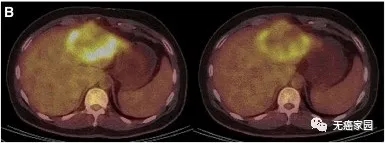

患者P9的PET/CT显示肿瘤活性明显减弱